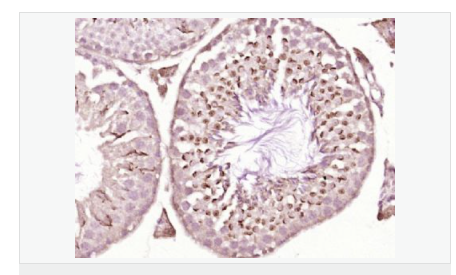

產(chǎn)品應(yīng)用WB=1:500-2000 ELISA=1:5000-10000 IHC-P=1:100-500 IHC-F=1:100-500 Flow-Cyt=1ug/test ICC=1:100-500 IF=1:50-200 (石蠟切片需做抗原修復(fù))

細(xì)胞定位細(xì)胞核 細(xì)胞漿